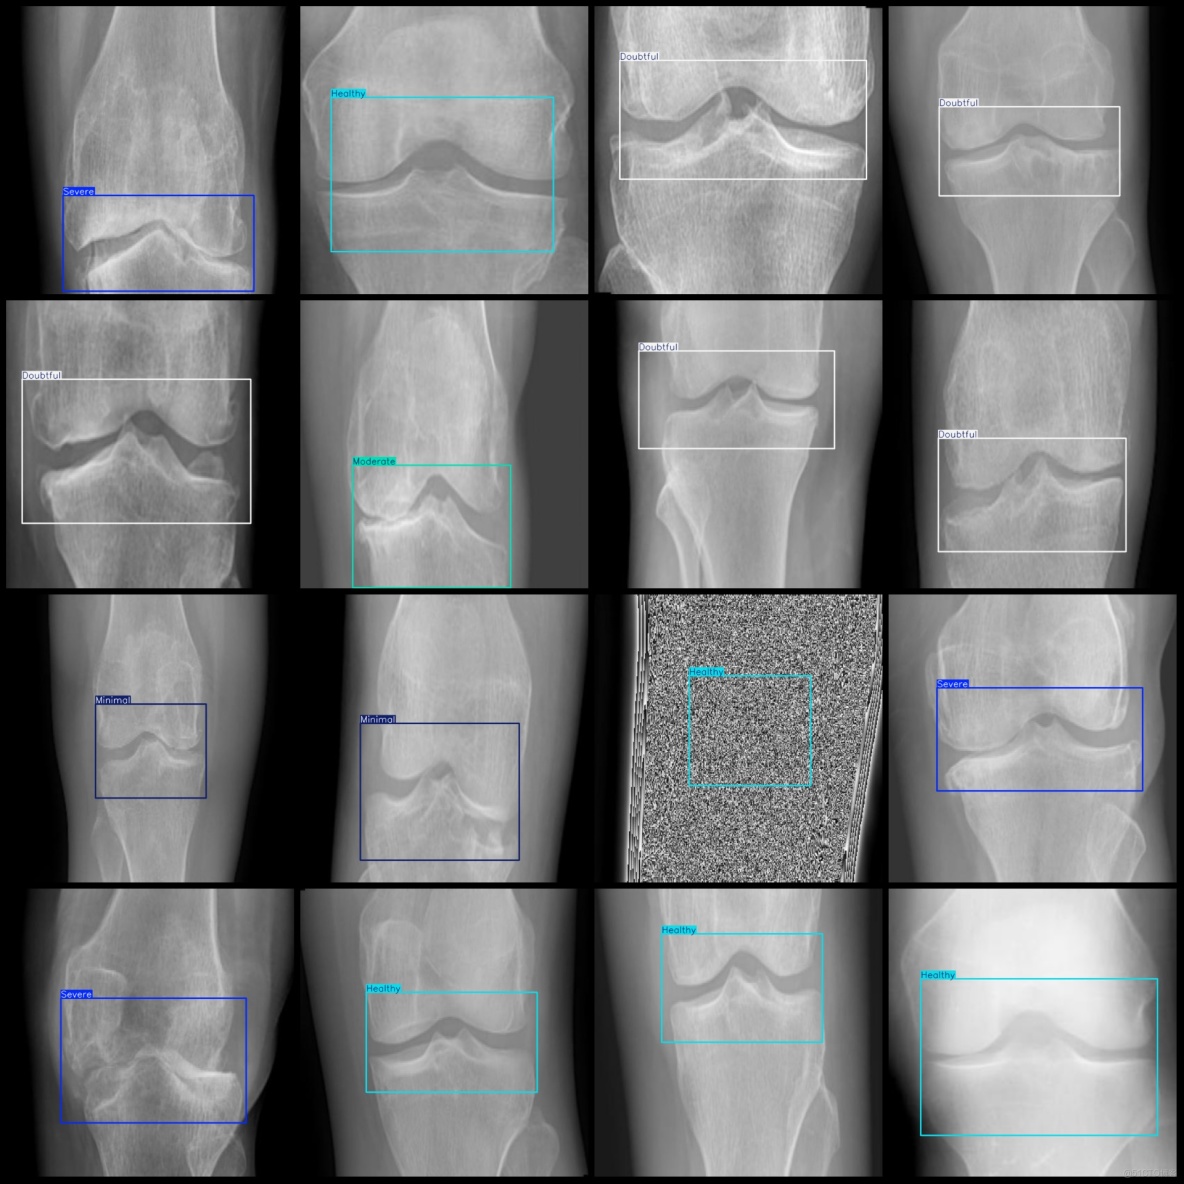

圖片預覽:

智慧醫療膝蓋骨關節炎嚴重程度檢測數據集VOC+YOLO格式8000張5類別_xml文件

智慧醫療膝蓋骨關節炎嚴重程度檢測數據集VOC+YOLO格式8000張5類別_數據集_02

標註類別名稱(注意yolo格式類別順序不和這個對應,而以labels文件夾classes.txt為準):["Doubtful","Healthy","Minimal","Moderate","Severe"]

每個類別標註的框數:

Doubtful (待定) 框數 = 1414

Healthy (健康) 框數 = 3700

Minimal (極輕度) 框數 = 819

Moderate (中度) 框數 = 730

Severe (重度) 框數 = 1337